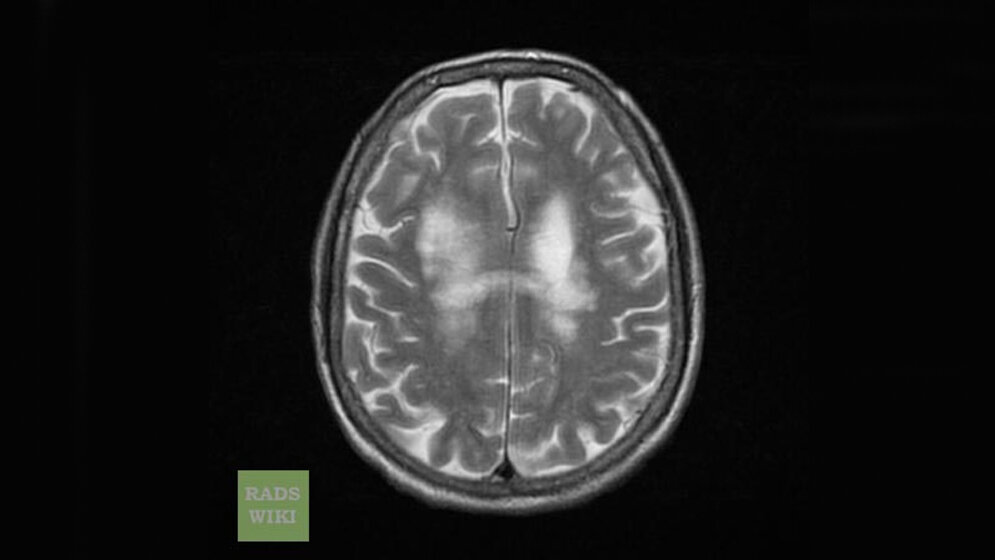

Ebenso viele Patienten mit PML wie Wiendl untersuchte das französische Forscherteam um Dr. Jérôme Hodel von der Universität Lille mehrmals im Krankheitsverlauf mit einem besonders leistungsstarken Magnetresonanztomographen (MRT). Als Vergleichsgruppe dienten 80 weitere Studienteilnehmer ohne PML, die entweder an Multipler Sklerose erkrankt waren oder an einer möglichen Vorstufe, dem klinisch isolierten Syndrom. Die Auswertung der Bilder ergab, dass 18 der 20 PML-Patienten ein charakteristisches punktförmiges Läsionsmuster im Gehirn hatten, darunter alle 14 Patienten, die das MS-Medikament Natalizumab bekommen hatten. In der Kontrollgruppe wurde das „Pünktchenmuster“ dagegen kein einziges Mal beobachtet.

Aufnahmen, die bereits vor dem Ausbruch der PML bei 9 Patienten unter Natalizumab angefertigt wurden, zeigten das Muster zudem bei 7 dieser Patienten. Die Läsionsmuster seien deshalb „ein hochspezifisches Merkmal der PML und vielleicht das erste Bildgebungsmerkmal in der vorsymptomatischen Phase mit potenziellen Implikationen für die Versorgung der Patienten“, schreiben Hodel und Kollegen.

„Die MRT ist integraler Bestandteil in der Gesamtbetrachtung der Multiplen Sklerose, und die frühzeitige Diagnose einer PML hat entscheidenden Einfluss auf die weitere Prognose“, bekräftigt der Neuroradiologe Lukas. Bei gefährdeten Patienten könnten die beschriebenen Läsionsmuster den Verdacht auf eine PML erheblich unterstützen. Bemerkenswert sei schließlich, dass das Läsionsmuster sogar in solchen Fällen vorhanden war, bei denen man den eigentlichen Auslöser der Krankheit – das JC-Virus – nicht einmal mit einem hochempfindlichen Gentest (PCR) nachweisen konnte.